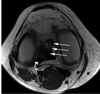

Mas ligamentos meniscales. Los oblicuos laterales. Fig. 5.7 La imagen FSE axial (PD) muestra el ligamento oblicuo lateral (flechas) que conecta el asta posterior del menisco medial (flecha curvada) con el cuerno anterior del menisco lateral